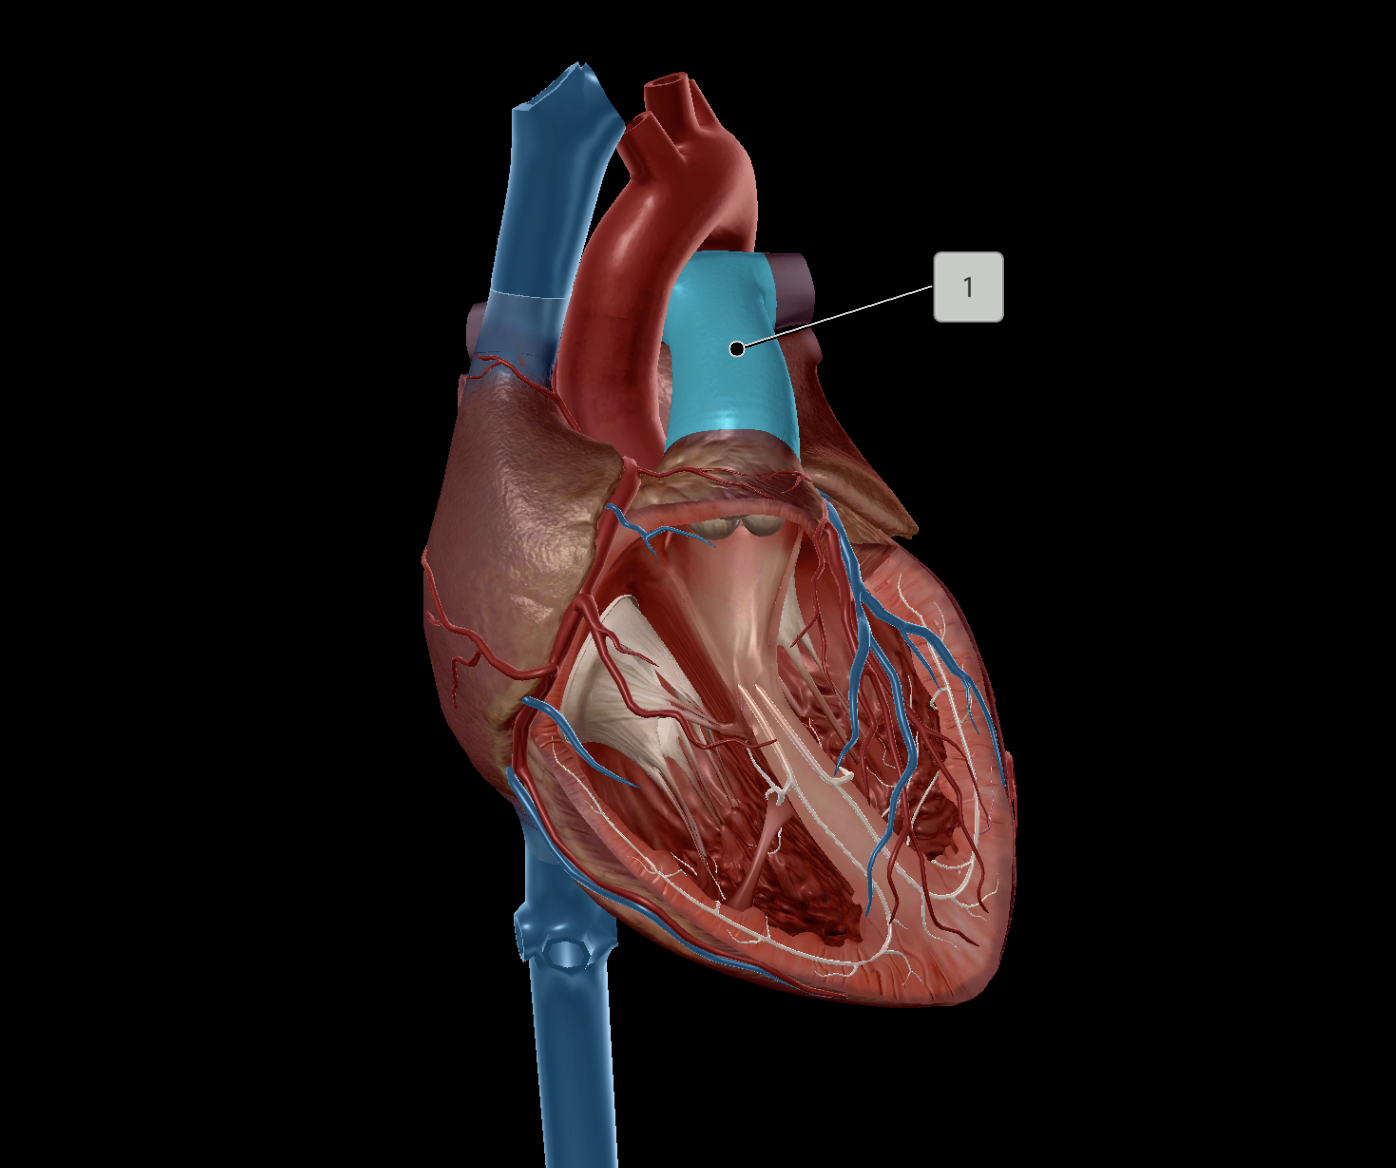

Pulmonary Trunk

Pulmonary Artery

Pulmonary Valve

Right Ventricle

Right Atrium

Left Atrium

Left Ventricle

Interventricular Septum

Interatrial Septum